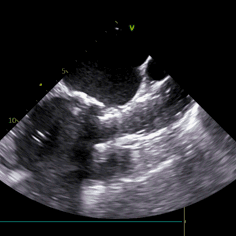

术后流速

术后即刻血压135/65mmHg,狭窄解除,释放后超声测量瓣下支架长度6mm标准位释放瓣膜位置完美。整台手术用时不足1.5小时,麻醉、超声等团队全程协作为手术顺利完成保驾护航。